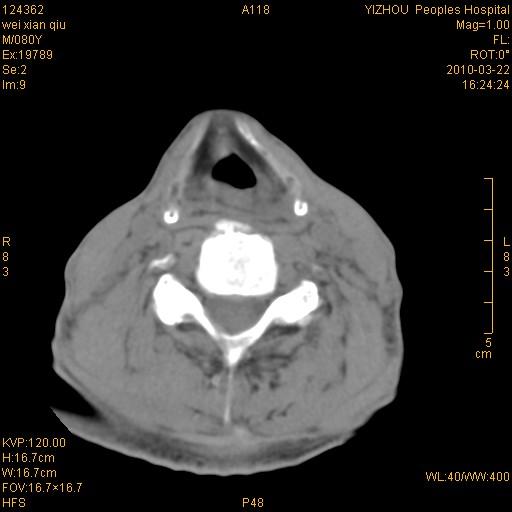

标题: CT25263:喉部占位?

男,80岁.声嘶三月余.

喉前庭右侧壁明显增厚,并见向内突出的软组织密度新生物,表面光滑,其后方软组织层次尚清晰,多考虑:喉部乳头状瘤!建议喉镜并病检!

考虑喉癌;建议行喉镜检查(活检)进一步明确诊断。

右侧声们下区新生物,建议行喉镜检查(活检)进一步明确诊断。